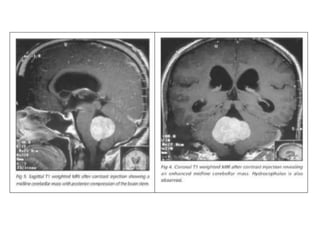

Sagittal , T1 weighted Gadolinium contrast enhancement – Medulloblastoma with

metastatic spread to the meninges within the posterior fossa and with a large

intramedullary deposit.